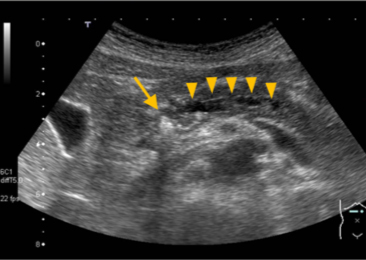

【慢性膵炎の超音波画像】

膵管の中に白い膵石(矢印)がはまり込んでいる。

膵液の流れが悪くなった結果、膵管が太くなっている(矢頭)。